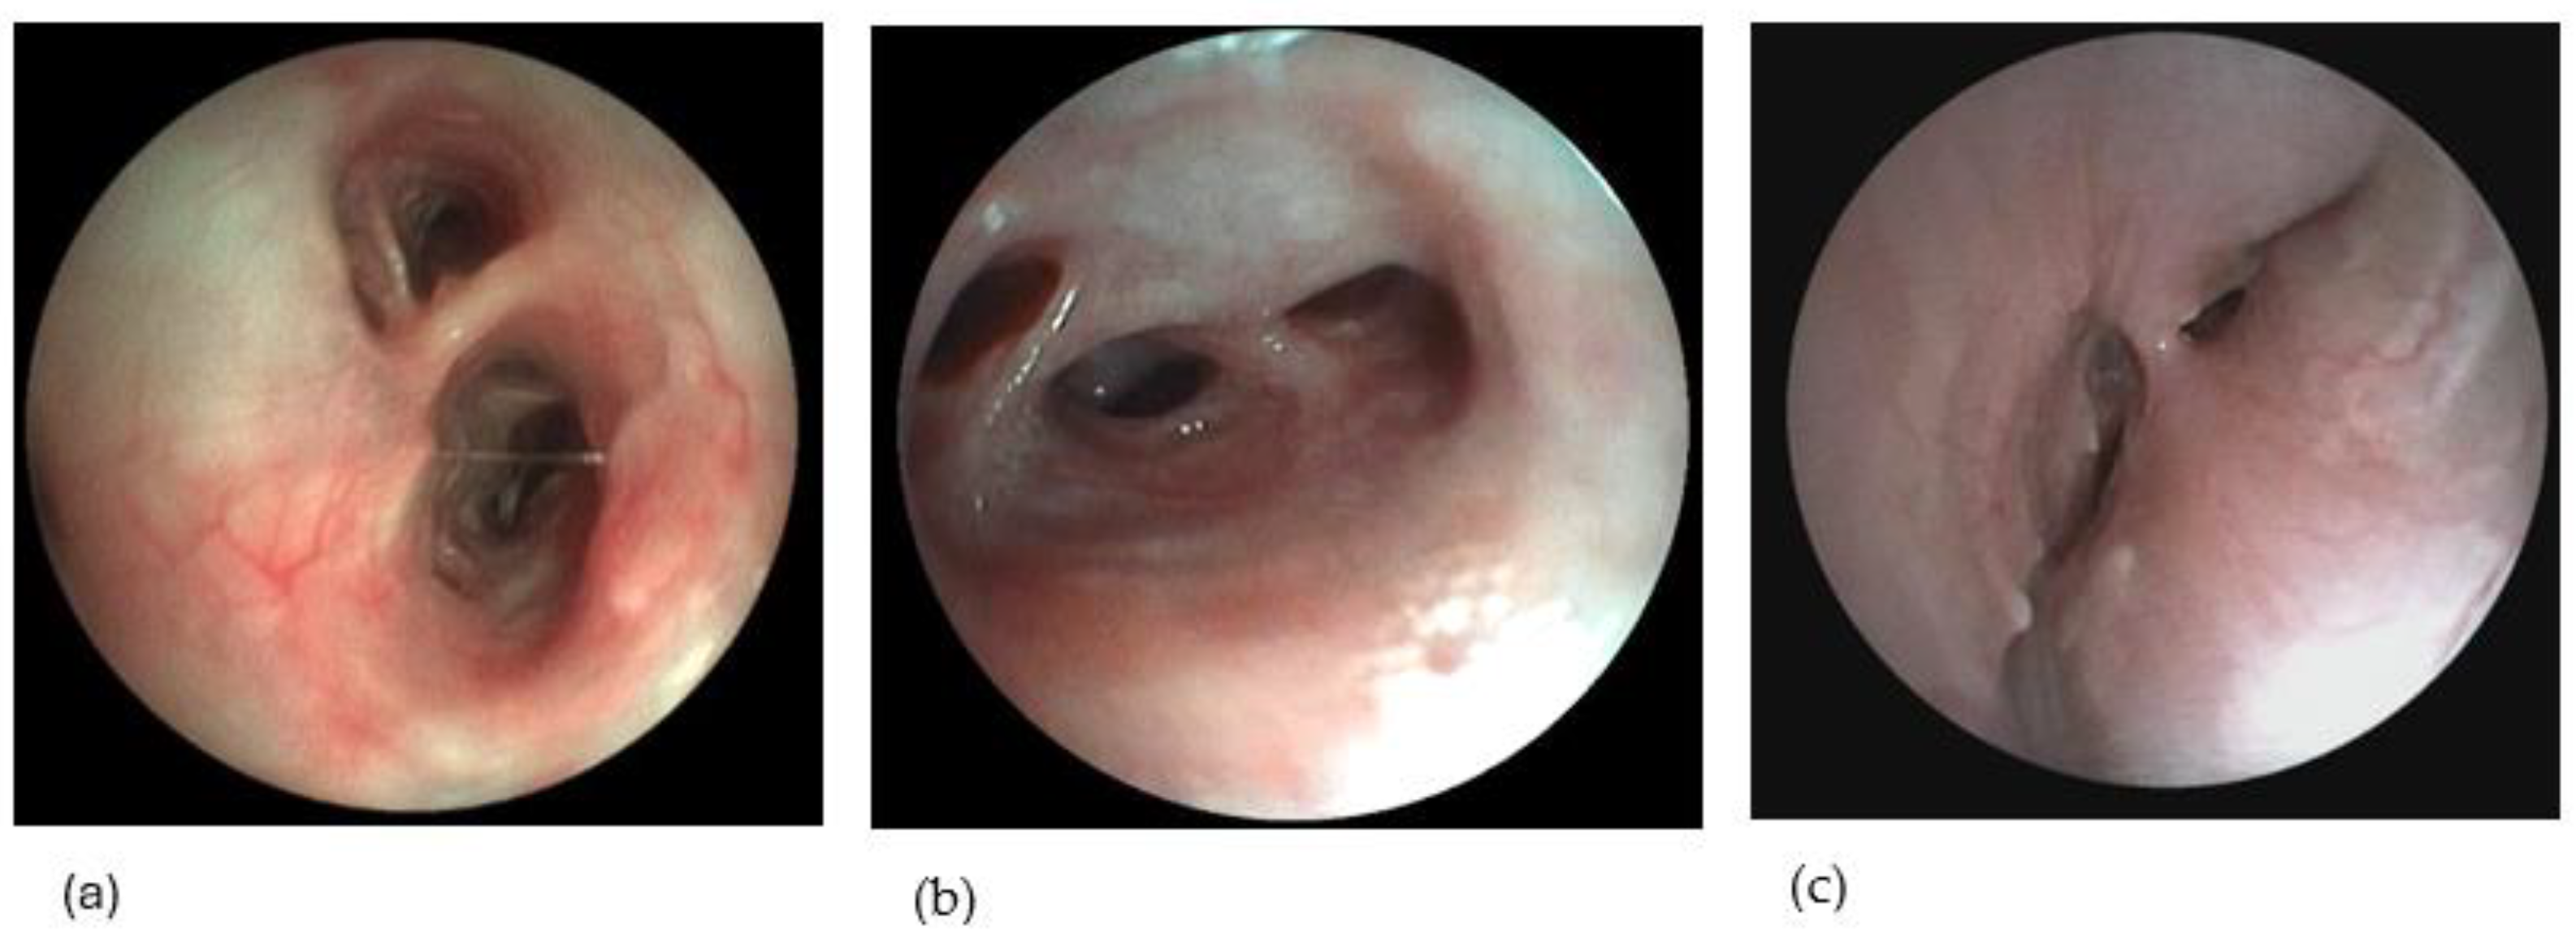

3.1.1. Group Allocation Based on Bronchoscopy

3.1.6. BALF Cytological and Microbiological Analysis